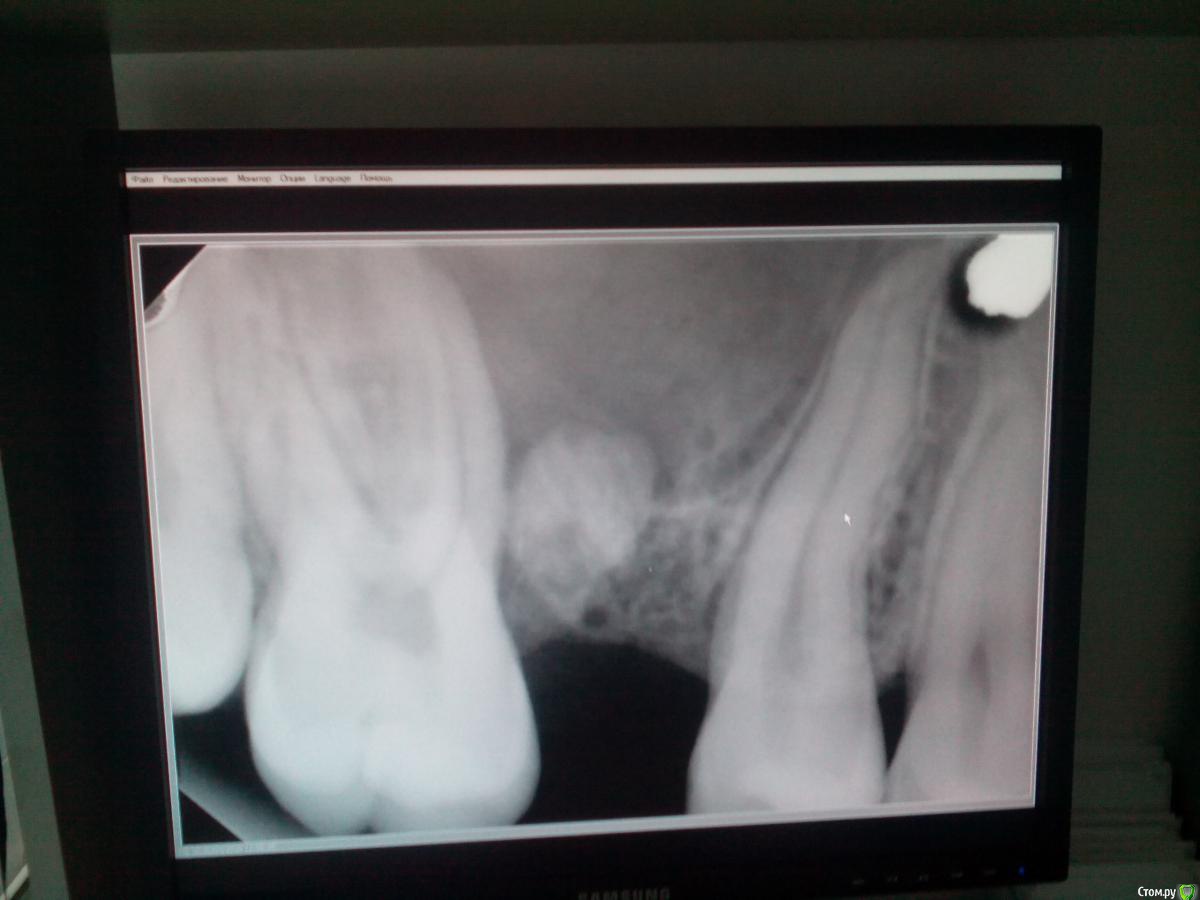

Анна Русина Опубликовано 20 апреля, 2016 Поделиться Опубликовано 20 апреля, 2016 (изменено) Здравствуйте уважаемые! Подскажите, как такое возможно? 2,5 года назад удалила зуб верхний коренной жевательный, рентген делали - было пусто. Третий день болит ямка та, языком чувствую что она надулась., ночью было очень больно сейчас вроде меньше. Фото ренгена сделанного 10 минут назад прилагаю Изменено 20 апреля, 2016 пользователем Анна Русина Ссылка на комментарий